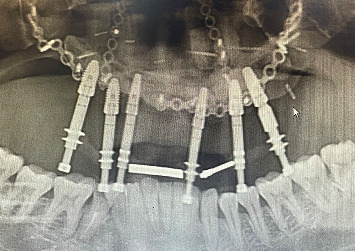

For managing peri-implantitis, a variety of treatment modalities involving both surgical and nonsurgical methods including implantoplasty have been proposed. Implants that are placed in a free fibula flap are more prone to peri-implantitis due to the absence of firm, keratinized mucosa. Prosthetic design that offers adequate hygiene access should be designed whenever possible; otherwise, it may lead to the accumulation of plaque or biofilm that may lead to peri-implant diseases. Implantoplasty, which is performed in advanced peri-implantitis cases that cause exposure of implant threads, has been proposed as a reliable approach to preventing progressive peri-implant bone loss by modifying the exposed implant surface. This clinical report details the management of severe peri-implant bone loss in a maxilla reconstructed with a free fibula flap by combining soft tissue management, implantoplasty, and prosthetic rehabilitation.